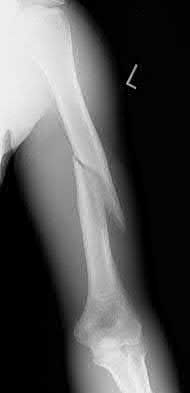

1012) A 54-year-old woman sustains the injury seen in Figures 71a and 71b. The injury involves her nondominant extremity. What should the patient be told regarding her expected outcome?

1. She should expect to return to full function and regain full range of elbow motion.

2. Reduction and casting has equivalent outcomes to those of surgical treatment.

3. This type of injury is associated with a high rate of complications.

4. Nerve dysfunction is commonly associated with this injury.

5. Ulnohumeral instability is the major complication seen with this fracture pattern.

Corrent answer: 3

This is a Bado type 2 (posterior) Monteggia lesion, which is associated with higher rates of complications than other types of Monteggia lesions. The injury is associated with indirect high-energy trauma and less often pathologic causes. Of the four types of Monteggia lesions, the type 2 or posterior type is associated with the worst prognosis. These injuries are best treated surgically with dorsal plating of the ulna and reduction with fixation or arthroplasty of the radial head. The major complications seen with this injury pattern are nonunion and plate failure. Almost all patients have some loss of elbow range of motion. Satisfactory results based on functional scores for this injury are not universal. Neurologic injury and ulnohumeral instability are unusual with this type of injury. Full functional recovery is not expected with nonsurgical management.